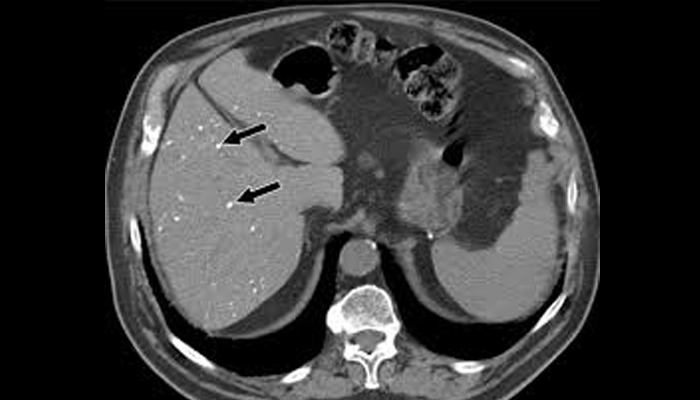

Hình ảnh nốt vôi hóa ở gan trên phim chụp Xquang

Nốt vôi hóa gan thực chất là hiện tượng canxi lắng đọng bất thường ngay trong nhu mô gan. Trên các phương tiện chẩn đoán hình ảnh, chúng sẽ xuất hiện dưới dạng các đốm tăng âm (siêu âm) hoặc các nốt có đậm độ cao (chụp CT).